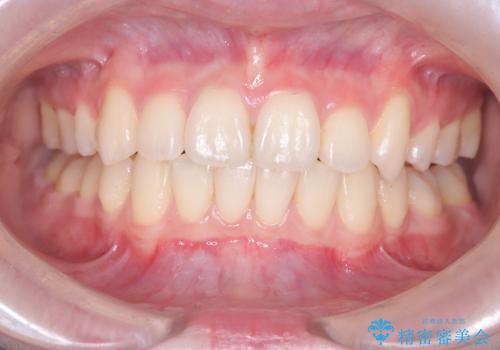

前歯のがたつきをマウスピース矯正で改善。IPRと遠心移動による非抜歯インビザライン治療

担当医 河口智英